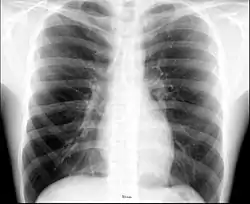

X-ray image of the chest showing the internal anatomy of the rib cage, lungs and heart as well as the inferior thoracic border–made up of the diaphragm.

The contents of the thorax include the heart and lungs (and the thymus gland); the major and minor pectoral muscles, trapezius muscles, and neck muscle; and internal structures such as the diaphragm, the esophagus, the trachea, and a part of the sternum known as the xiphoid process. Arteries and veins are also contained – (aorta, superior vena cava, inferior vena cava and the pulmonary artery); bones (the shoulder socket containing the upper part of the humerus, the scapula, sternum, thoracic portion of the spine, collarbone, and the rib cage and floating ribs).